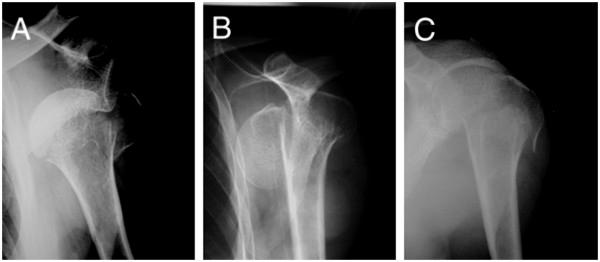

A 53-year old postman suffered from shoulder dislocation with an undisplaced fracture of the humeral anatomical neck which was initially undiagnosed. After the first attempt to reduce the dislocation of the shoulder joint by Stimson's method, complete displacement of the fractured humeral anatomical neck occurred. By closed reduction under general anesthesia, the displaced humeral head was successfully reduced and was subsequently treated by conservative therapy using sling immobilization. Follow-up by MRI two years later showed no evidence of avascular necrosis of the humeral head. The patient showed a satisfactory range of motion of the affected shoulder joint.In the present case, the blood supply was partially preserved because a part of the lesser tubercle remained attached to the displaced humeral head.

一名53岁的邮递员,患有肩关节脱位,伴有肱骨解剖颈无移位骨折,最初未被诊断出来。在首次尝试通过斯廷森法复位肩关节脱位后,肱骨解剖颈骨折出现了完全移位。通过全身麻醉下的闭合复位,成功复位了移位的肱骨头,随后采用吊带固定进行保守治疗。两年后的MRI随访显示,没有肱骨头缺血性坏死的迹象。患者患侧肩关节的活动范围令人满意。在本病例中,由于部分小结节仍附着于移位的肱骨头,血供得以部分保留。